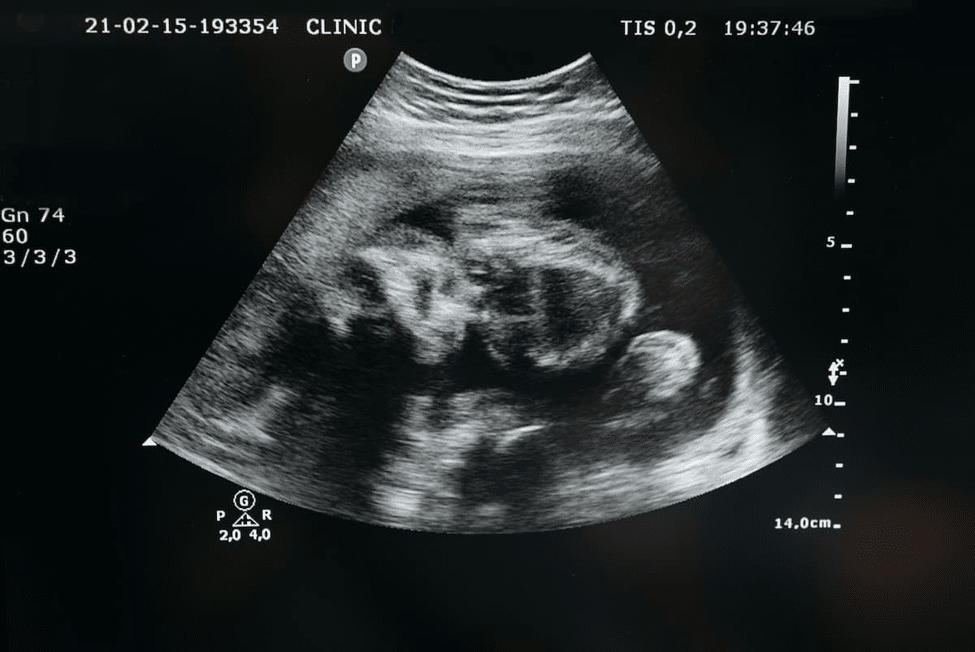

34 Weeks Fetal Development

At 34 weeks, your baby is rapidly growing and developing vital organs. At this stage, most systems are functioning well, though a few still need fine-tuning before birth.

Brain and Lung Growth

To start with, your baby’s brain and lungs are now entering a crucial growth phase.

- The brain is expanding quickly, forming millions of new neural connections each day.

- The lungs continue to produce surfactants, a substance that helps your baby breathe easily after birth.

- Meanwhile, the baby practices breathing movements inside the womb, preparing for life outside.

In addition, the baby’s bones are hardening, and layers of fat are building under the skin, making your little one look plumper and ready for delivery.

34 Week Fetus Weight and Size

On average, the 34-week fetus weight is around 2.1 to 2.3 kilograms (4.6 to 5 pounds).

As for the 34-week baby size, your little one measures about 17 to 18 inches long, roughly the length of a butternut squash.

As a result, your baby now takes up most of the space in your uterus that’s why you may feel stronger kicks, rolls, and even hiccups more often!